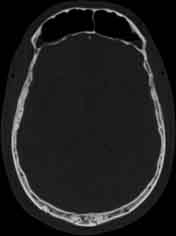

Visible Human male: Sectio transversalis 1084

CT

NMR

Pd T1 T2